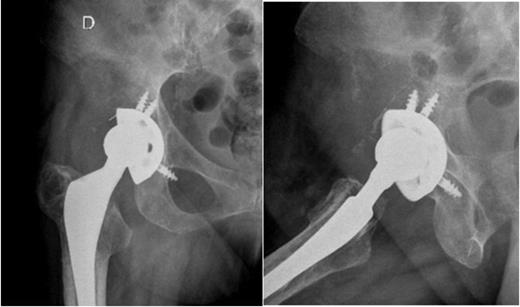

A 64-year-old woman presented with right hip pain of mixed characteristics with few months of evolution. She has had a fracture of the neck of the femur (Garden IV) after a fall nine years before, and undergone total hip arthroplasty with a cementless device (ART stem and ALIZE cup from Biomet, Warsaw, Indiana, USA). The patient followed our standard protocol for evaluation of pain after total hip arthroplasty, with plain radiographs and inflammatory markers (C-reactive protein and erythrocyte sedimentation rate). The inflammatory markers were within the normal range and comparing past and present radiographs there were signs of cup instability with osteolysis lines larger than 2 mm in zones I and II of De Lee and Charnley (Fig 1).

Right hip radiographs (lateral and AP) at the initial evaluation with osteolysis in zones I and II of De Lee and Charnley suggestive of cup loosening